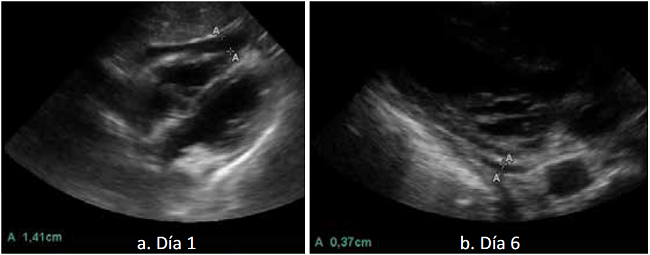

De agosto de 2017 hasta julio de 2018, el grupo de cirujanos de trauma de este hospital ha evaluado 45 pacientes clínicamente estables con trauma precordial. Se descartó la presencia de derrame pericárdico en la evaluación hecha con ultrasonido en 31 de ellos. Su evolución clínica no tuvo eventualidades.

De los 14 pacientes con derrame pericárdico identificado en la ecografía, cuatro recibieron observación clínica estrecha y seguimiento con ecografías diarias (figura 5). Ninguno presentó deterioro, requirió intervención quirúrgica o presentó complicaciones en el seguimiento a 28 días. Los 10 pacientes restantes fueron manejados con ventana pericárdica, la cual resultó negativa en cinco y positiva en los otros cinco. En cuatro de estos, se practicó una toracotomía o una esternotomía. El paciente restante fue tratado con drenaje y lavado del saco pericárdico y observación posoperatoria. En su evolución tampoco hubo complicaciones y no requirió intervención quirúrgica (Chica J, comunicación personal, Agosto de 2018) (figura 6).